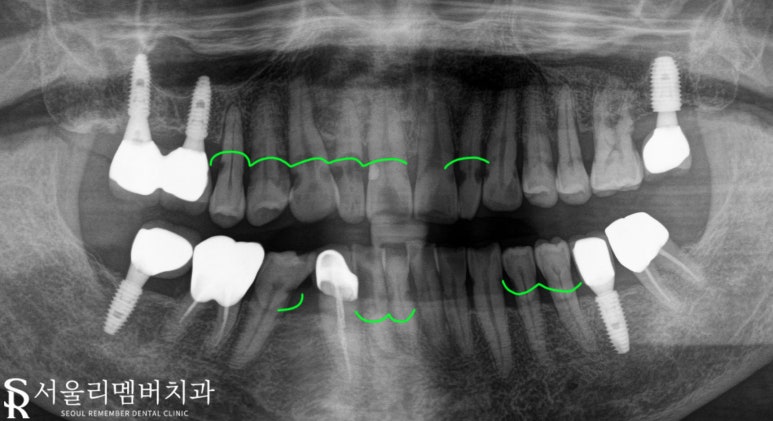

엑스레이 사진을 보면 많이 다릅니다.

초록색 표시 : 충치 감염된 부분

전반적으로 충치가 많이 번져있는

심각한 상태였습니다.

26번 치아는 잇몸 퇴축이

이루어져 뿌리가 나뉘는

분지구가 밖으로 드러나

그곳에 치석이 쌓여

우식으로 진행되어 있었고

이를 제외한 나머지 대부분의

우식은 치 경부 쪽에서

이루어져서 꽤 난도 있는

과정이 예상됩니다.